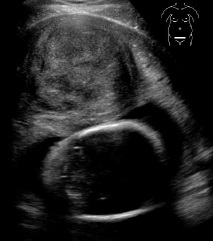

Τα ινομυώματα στην εγκυμοσύνη συχνά μεγαλώνουν σε μέγεθος, ακολουθώντας τη μεγέθυνση της ίδιας της μήτρας. Τις περισσότερες φορές δεν προκαλούν κανένα πρόβλημα στην εξέλιξη της κύησης. Σπάνια μπορεί να προκαλέσουν έντονο πόνο και πυρετό, καθώς νεκρώνονται από έλλειψη αιμάτωσης.